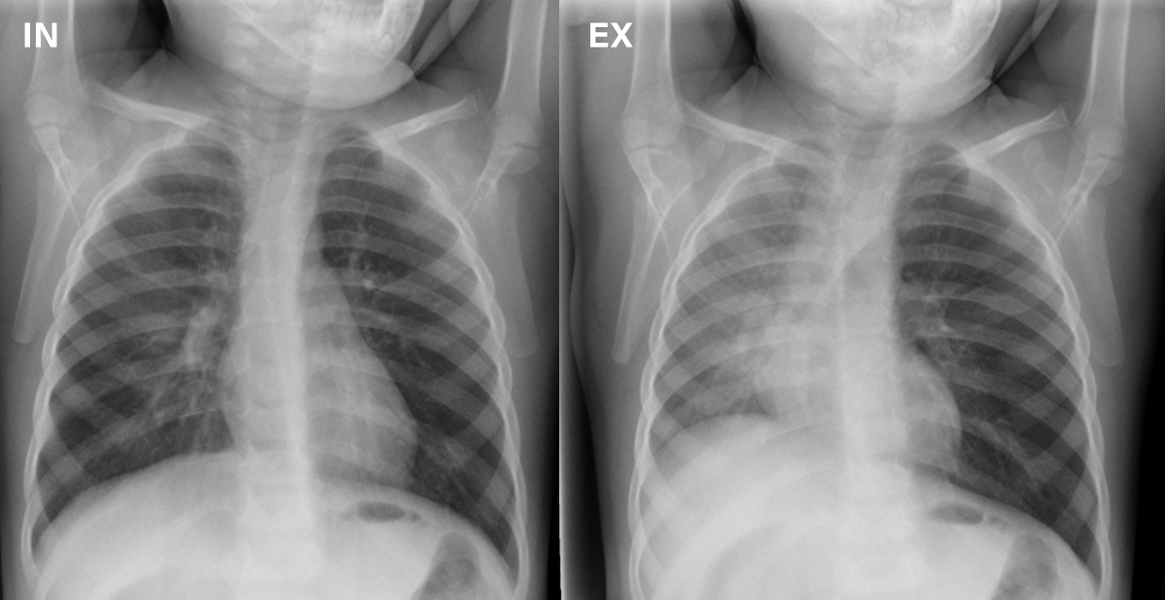

Airway Foreign Body